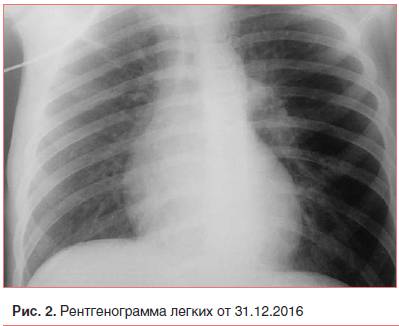

Локализация процесса вдоль корня легкого затрудняет рентгенологическую диагностику заболевания. Рентген в прямой проекции показывает расширение корня легкого, увеличение тени средостения, но дать более точные характеристики не представляется возможным. Более детальную информацию может дать компьютерная томография. Однако даже при качественном изображении остаются иногда вопросы.

Основным методом диагностики прикорневой пневмонии являются рентгенологические методы исследования. На рентгенограммах врач может увидеть локализацию воспаления, дифференцировать прикорневое воспаление лёгких от других заболеваний дыхательных путей. Но при прикорневой пневмонии интерпретация рентгенографического исследования может быть затруднительной. Затемнение от воспалённого очага часто наслаивается на корень лёгкого. В результате легочный корень на рентгеновском снимке «расширяется», что может указывать на новообразование или туберкулёз.